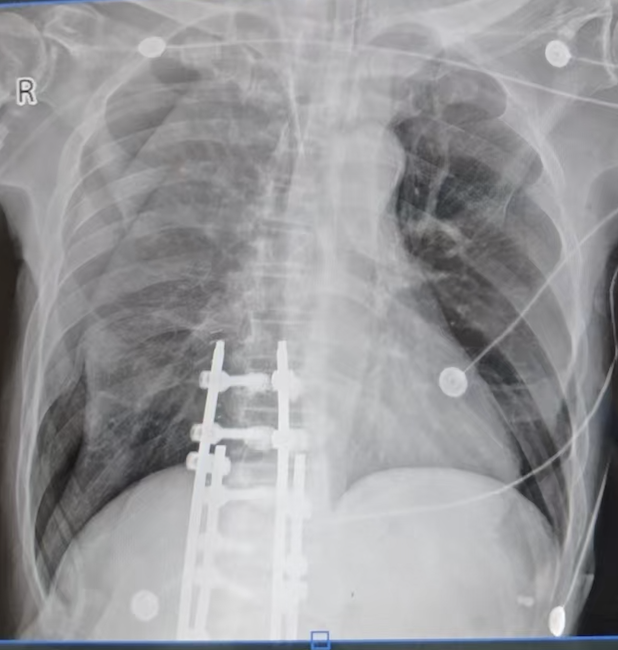

更像气胸了,氧合状态仍正常,气胸怀疑因此复查肺部CT。

排除气胸,和放射科医生沟通觉得也很像气胸,只能怀疑伪影。

你觉得可能是什么原因造成类似气胸的表现的?